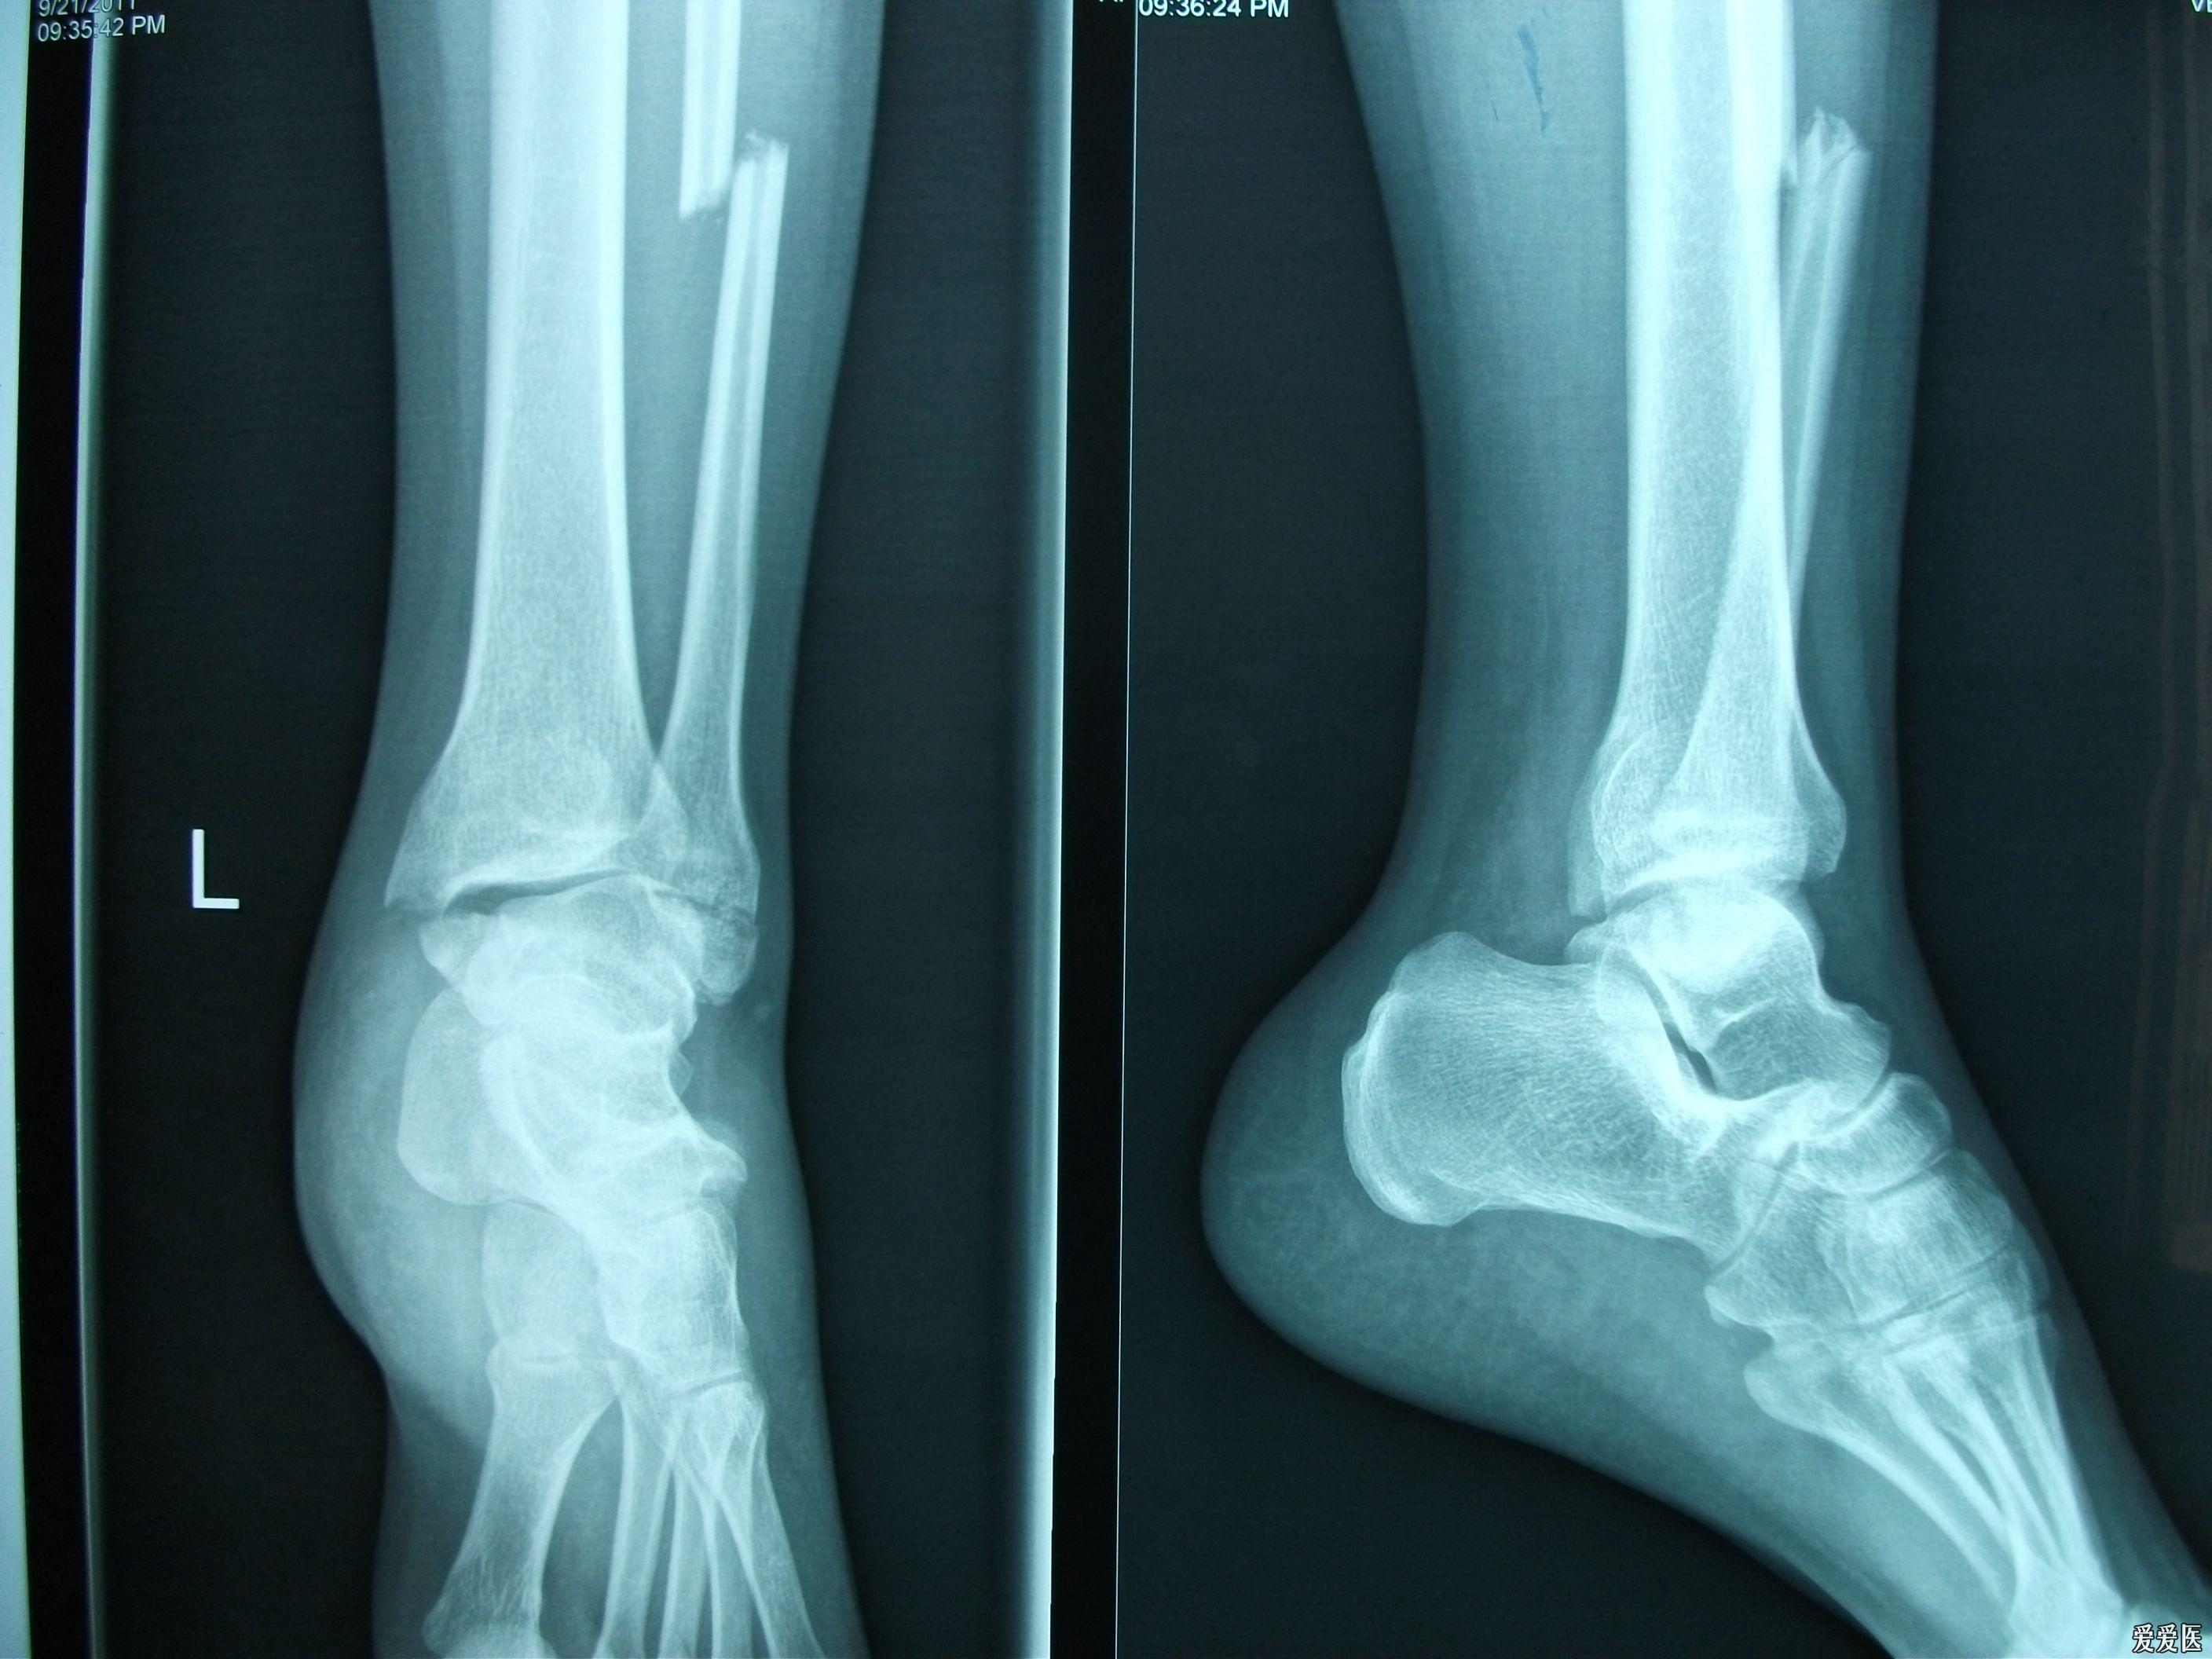

丁香园论坛>骨科>帖子详情>看着腓骨长度没问题,旋转没问题,踝穴也

左踝关节肿胀 辅助检查:x线片提示:左踝关节骨折,左侧腓骨骨折 临床